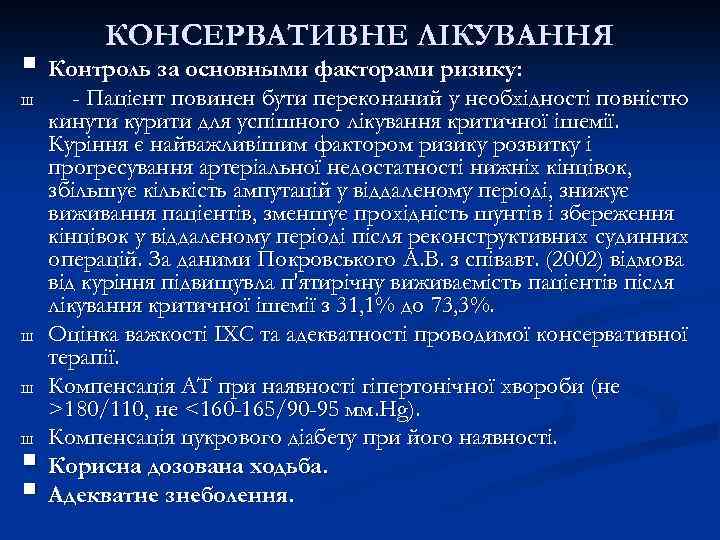

КОНСЕРВАТИВНЕ ЛІКУВАННЯ § Контроль за основными факторами ризику: Ш Ш § § - Пацієнт повинен бути переконаний у необхідності повністю кинути курити для успішного лікування критичної ішемії. Куріння є найважливішим фактором ризику розвитку і прогресування артеріальної недостатності нижніх кінцівок, збільшує кількість ампутацій у віддаленому періоді, знижує виживання пацієнтів, зменшує прохідність шунтів і збереження кінцівок у віддаленому періоді після реконструктивних судинних операцій. За даними Покровського А. В. з співавт. (2002) відмова від куріння підвищувла п'ятирічну виживаємість пацієнтів після лікування критичної ішемії з 31, 1% до 73, 3%. Оцінка важкості ІХС та адекватності проводимої консервативної терапії. Компенсація АТ при наявності гіпертонічної хвороби (не >180/110, не <160 -165/90 -95 мм. Hg). Компенсація цукрового діабету при його наявності. Корисна дозована ходьба. Адекватне знеболення.

КОНСЕРВАТИВНЕ ЛІКУВАННЯ § Контроль за основными факторами ризику: Ш Ш § § - Пацієнт повинен бути переконаний у необхідності повністю кинути курити для успішного лікування критичної ішемії. Куріння є найважливішим фактором ризику розвитку і прогресування артеріальної недостатності нижніх кінцівок, збільшує кількість ампутацій у віддаленому періоді, знижує виживання пацієнтів, зменшує прохідність шунтів і збереження кінцівок у віддаленому періоді після реконструктивних судинних операцій. За даними Покровського А. В. з співавт. (2002) відмова від куріння підвищувла п'ятирічну виживаємість пацієнтів після лікування критичної ішемії з 31, 1% до 73, 3%. Оцінка важкості ІХС та адекватності проводимої консервативної терапії. Компенсація АТ при наявності гіпертонічної хвороби (не >180/110, не <160 -165/90 -95 мм. Hg). Компенсація цукрового діабету при його наявності. Корисна дозована ходьба. Адекватне знеболення.